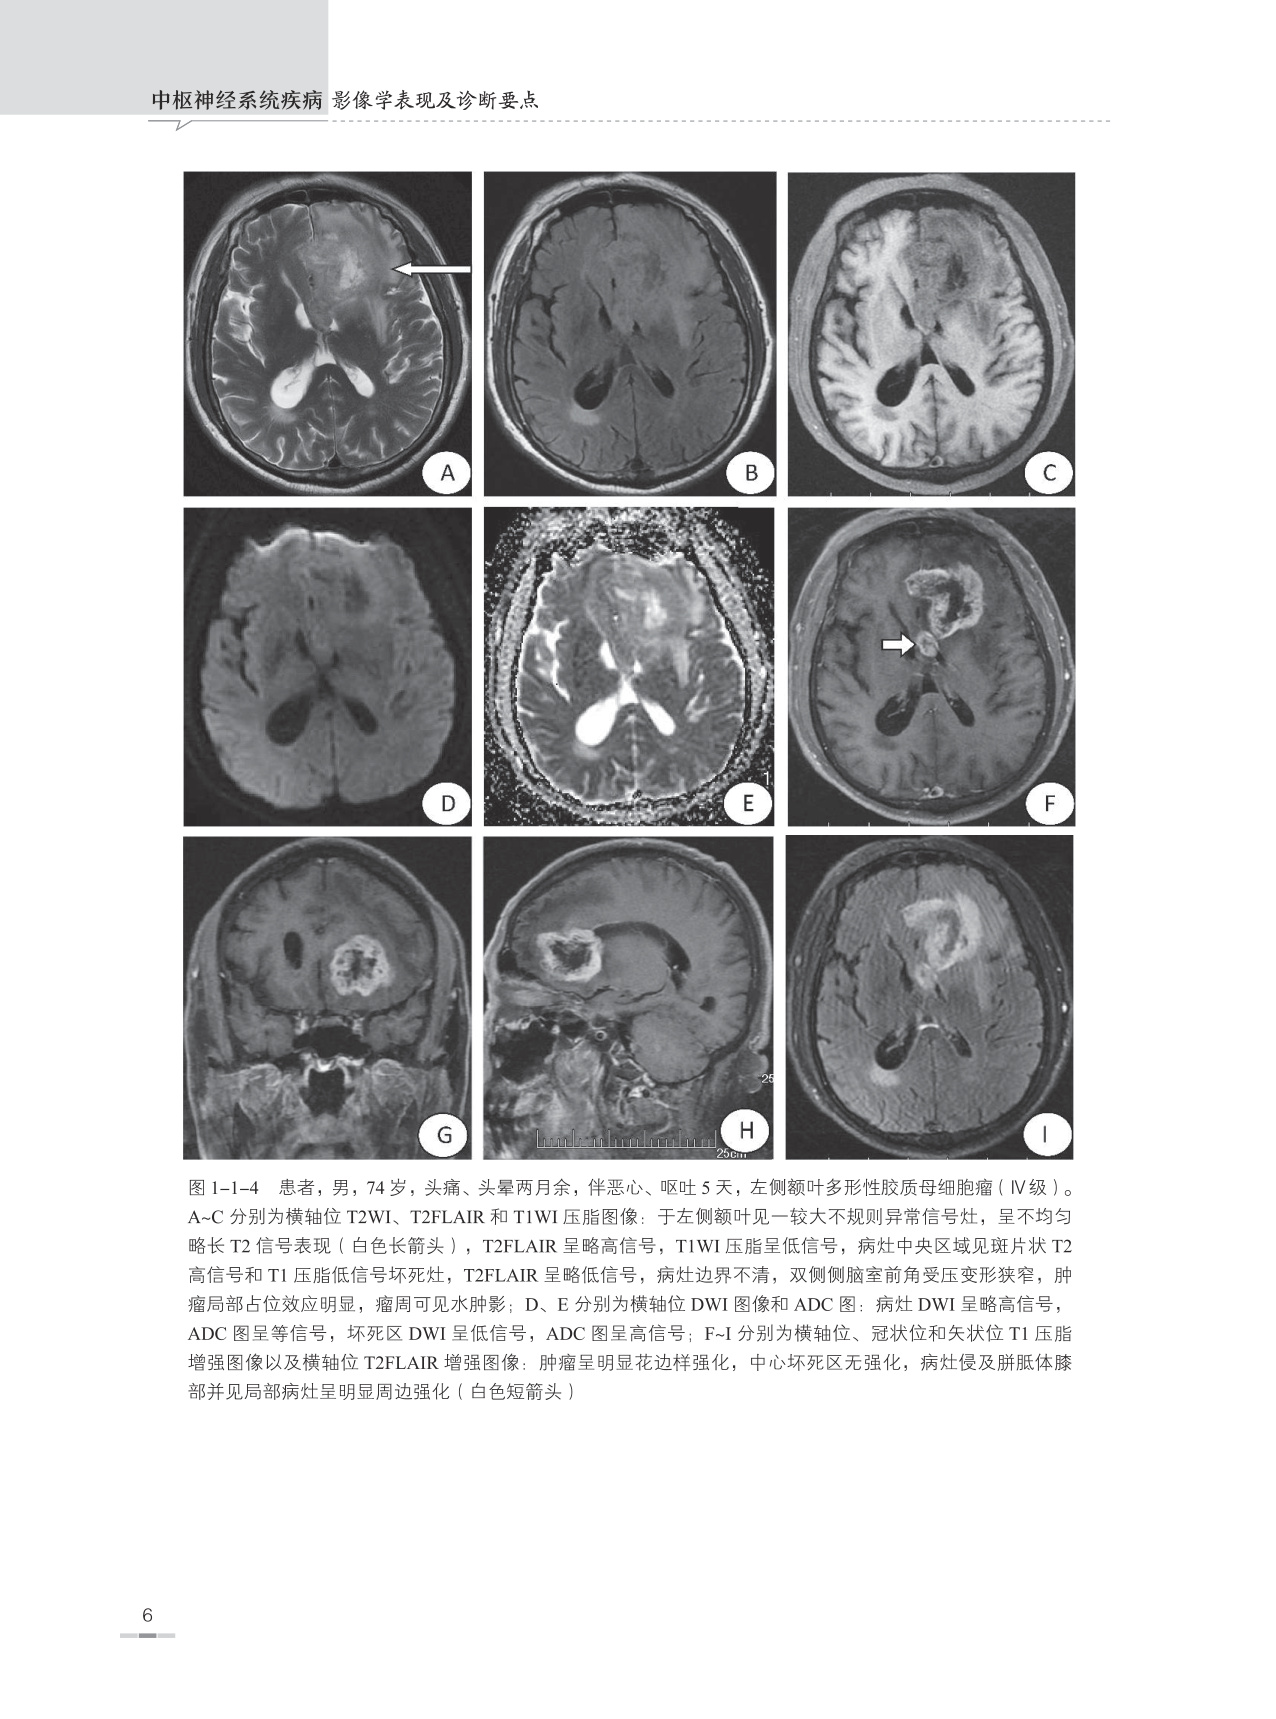

本书是根据作者本人多年临床工作经验并参考大量中外文献资料编写而成的,书内附图均为作者在40余年日常临床医学影像诊断工作中所收集留存的典型病例,书中对每一种疾病所涉及的内容包括疾病概述、流行病学、治疗与预后、病因、发病机制、病理、临床表现、影像学表现、典型病例图像、鉴别诊断及主要参考文献,以便读者能够全面理解和掌握疾病的临床及影像学表现特征。另外在每一种疾病论述开始之前附有本疾病的主要表现特征和诊断要点,以便读者能够快速掌握疾病的重点。

本书主要面向医学影像学诊断医师和医学影像学专业学生,并力求为各级医院神经内科、神经外科、急诊科、ICU、肿瘤科、脊柱外科、康复科、介入科、放疗科、病理科等相关科室以及全科医师提供神经系统疾病的影像学诊断信息,让广大的临床医师更好地了解医学影像学诊断技能在中